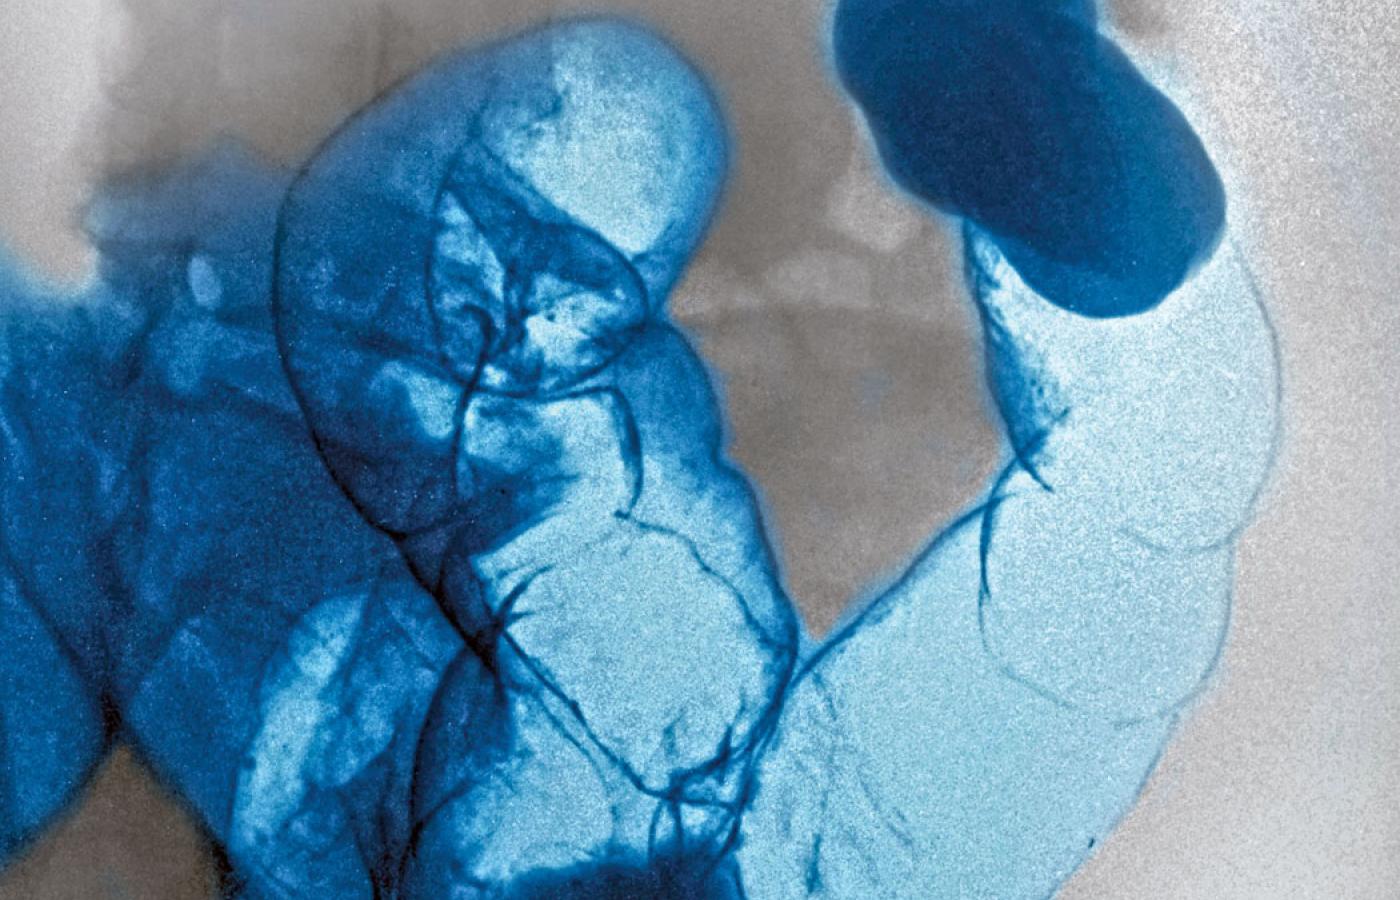

Rentgenowski obraz systemu trawiennego zaatakowanego przez rakaCavallini James/BEW Rentgenowski obraz systemu trawiennego zaatakowanego przez raka